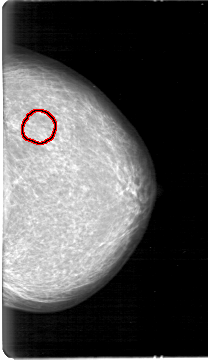

D_4026_1.LEFT_MLO

LEFT_MLO LINES 5386 PIXELS_PER_LINE 3181 BITS_PER_PIXEL 12 RESOLUTION 43.5 OVERLAY

FILE: D_4026_1.LEFT_MLO.OVERLAY

TOTAL_ABNORMALITIES 1

ABNORMALITY 1

LESION_TYPE MASS SHAPE OVAL MARGINS OBSCURED

ASSESSMENT 0

SUBTLETY 3

PATHOLOGY BENIGN

TOTAL_OUTLINES 1

BOUNDARY